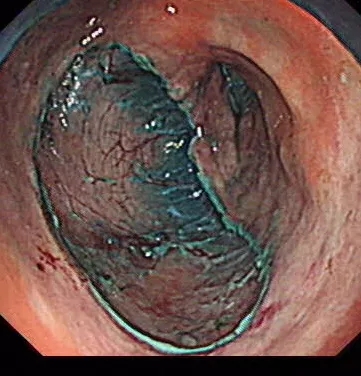

那胃镜下怎么将癌症切除呢?——ESD(内镜下粘膜剥离术)。这是近年来出现的一项新的微创治疗手段,虽然新,但该技术已经非常成熟,已成为早癌治疗的标准手术方式,让更多的早期消化道癌能够在内镜下一次性完全切除病变粘膜层,而保留完整的胃,免除了开腹手术的痛苦和器官的残缺。ESD与剖腹手术比较,具有创伤小、费用低、住院时间短、手术效果与开腹手术相当,且患者可一次接受多个部位多次治疗。

在近5个小时的手术后,胡大夫成功将陈先生胃里两处病变完整的切除了下来。病理结果也让人欣喜,病理显示内镜切除的非常完整,可以说将肿瘤干干净净、完完整整地切除了下来,并且该患者无需追加放化疗等后续治疗,只需胃镜随访即可。